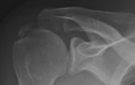

- Zentrum für Orthopädie und Unfallchirurgie

- Traumazentrum